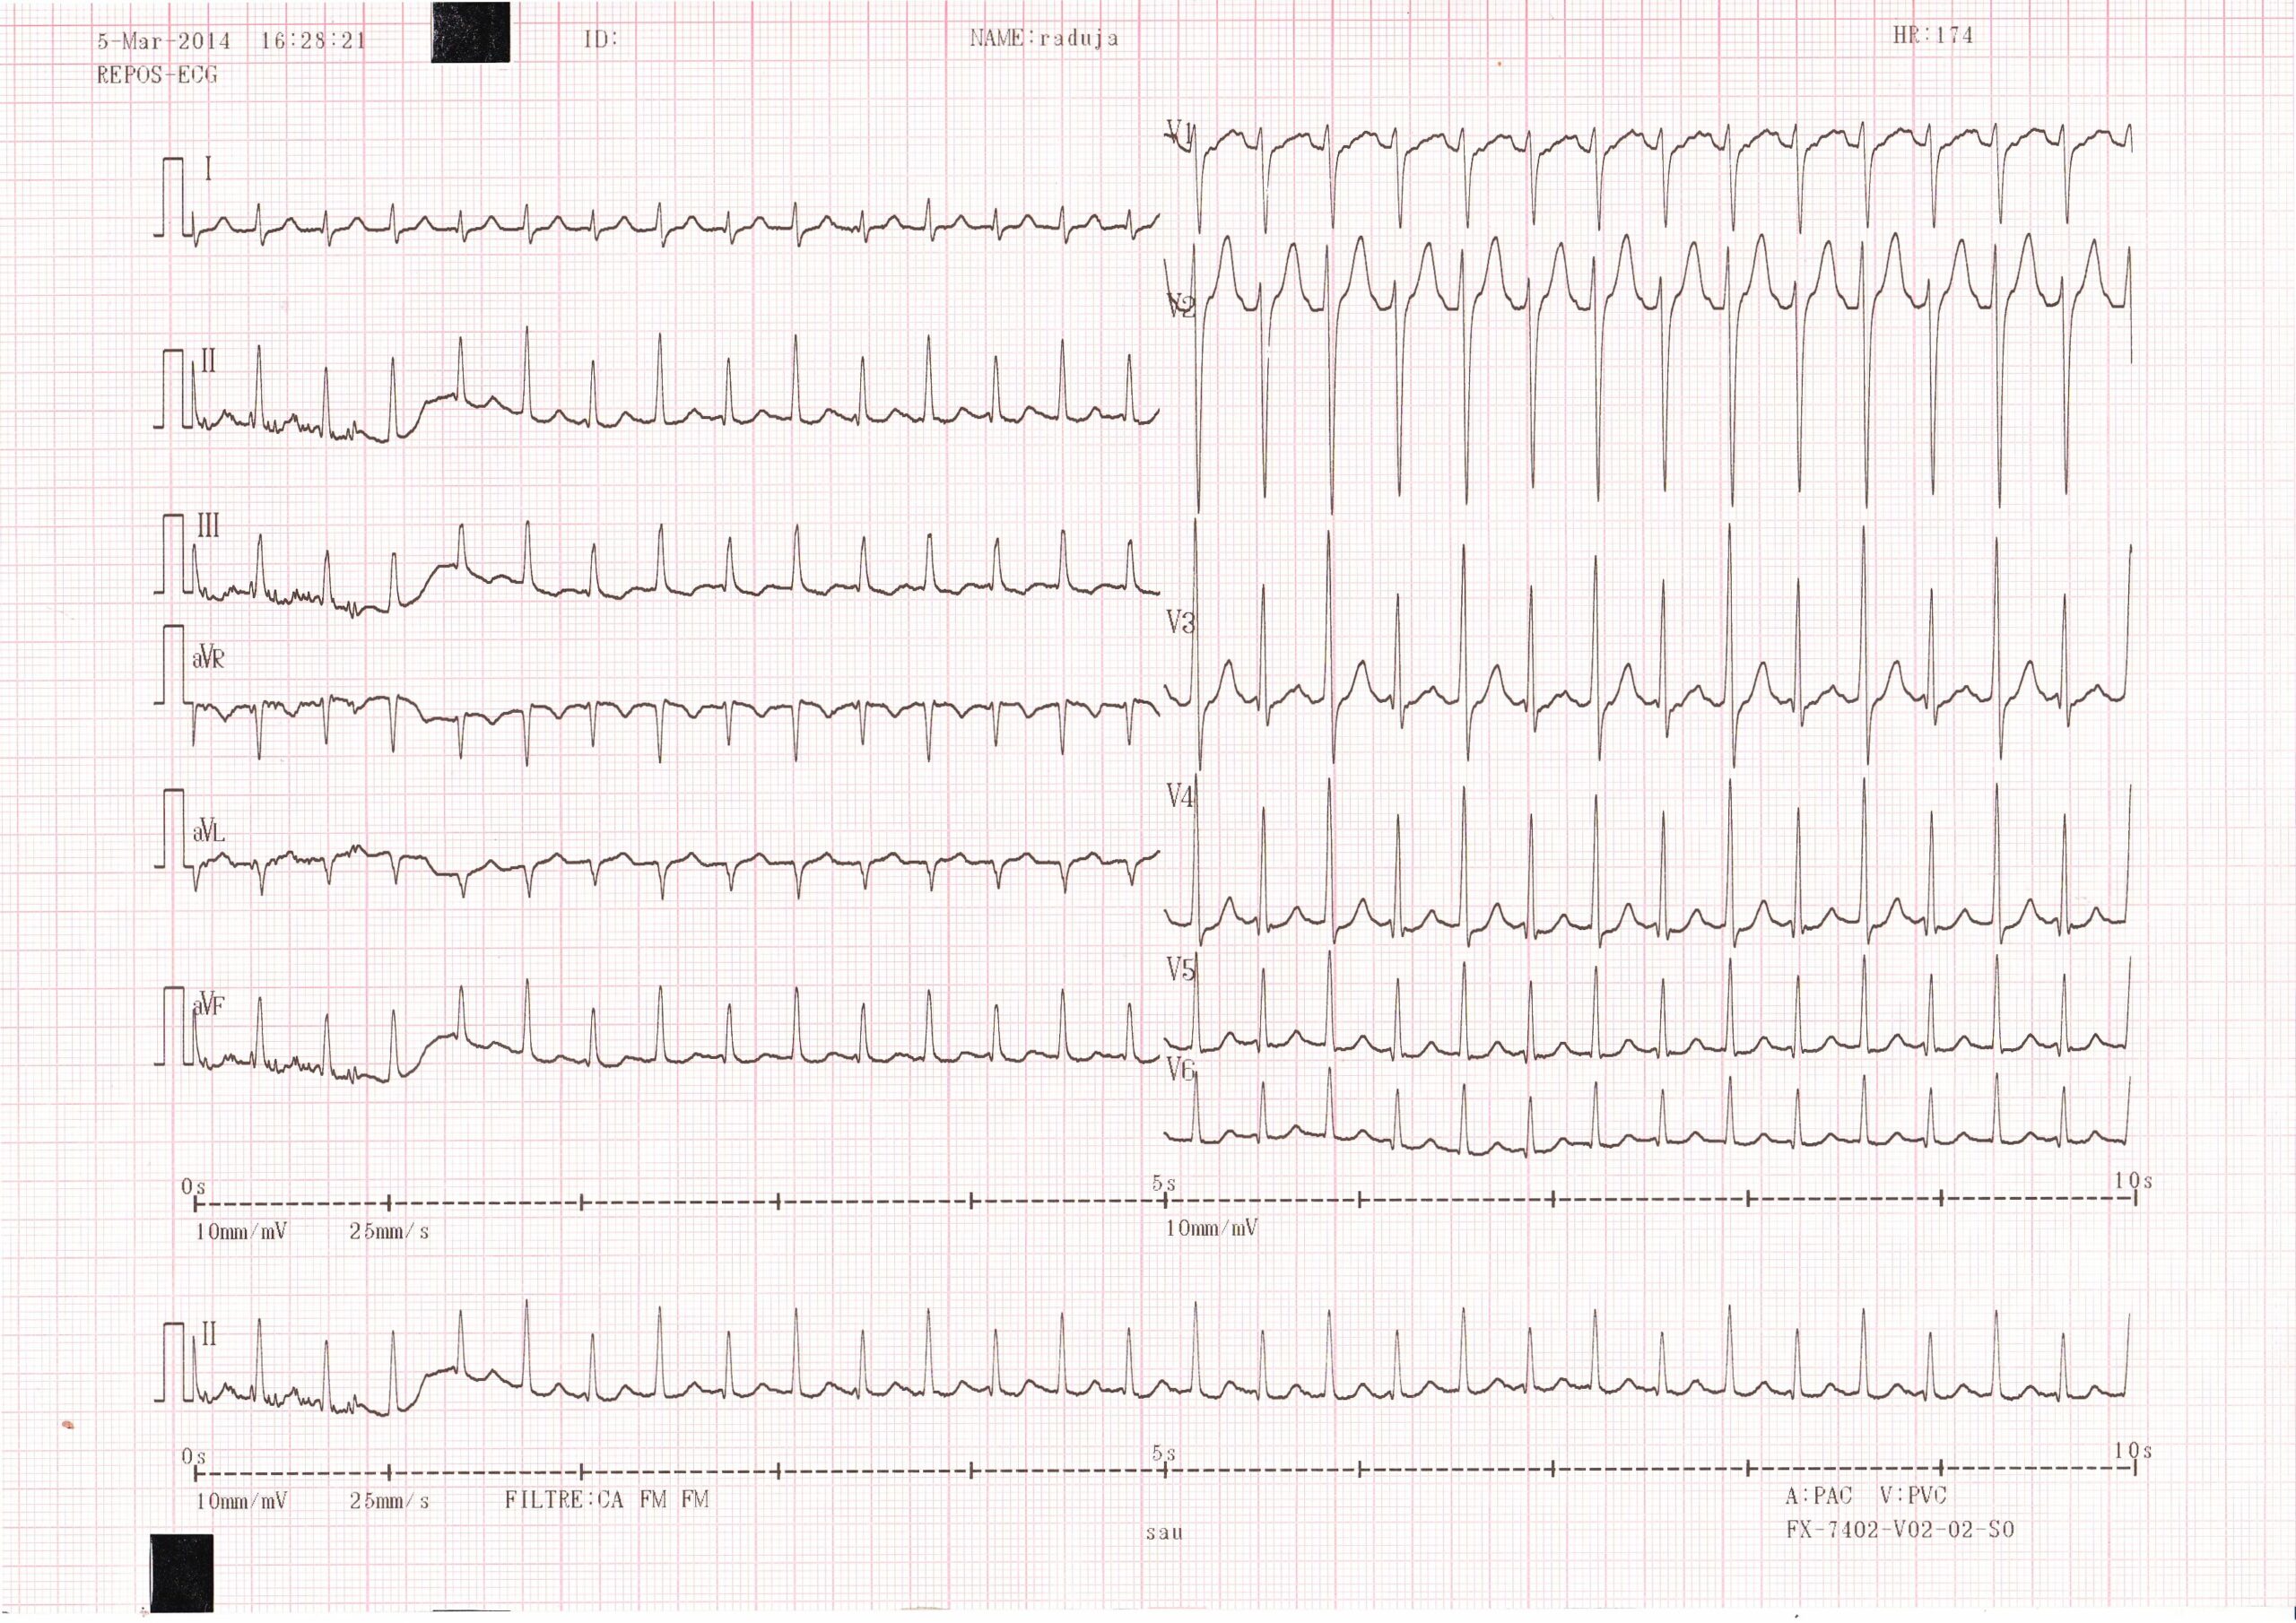

Ce tracé montre une tachycardie régulière à 170 bpm; les QRS sont fins permettant d’éliminer le diagnostic de tachycardie ventriculaire; à noter une alternance entre 2 morphologies de QRS fins (axes identiques mais amplitudes différentes); l’activité atriale est difficile à identifier rendant difficile la différenciation entre une tachycardie atriale et une tachycardie jonctionnelle (réentrée intranodale ou réentrée sur voie accessoire);

Les manifestations électriques lors d’une tachycardie atriale provenant de l’oreillette gauche dépendent non seulement de la séquence d’activation auriculaire gauche mais également du passage transseptal et de l’activation auriculaire droite qui en résulte. L’aspect électrocardiographique “typique” de flutter gauche est donc difficile à définir dans la mesure où plusieurs circuits sont possibles mais on retrouve généralement 4 caractéristiques plus ou moins spécifiques: 1) l’activité atriale est rapide, ectopique, régulière et monomorphe 2) l’onde de dépolarisation atriale en V1 est le plus souvent positive. Elle peut être bien voltée comme sur ce tracé mais peut être moins ample voire isoélectrique ; 3) une onde atriale positive en V1 peut correspondre à un flutter commun, il s’agit donc d’un signe très peu spécifique. La troisième caractéristique importante pour diagnostiquer ce type d’arythmie est que l’on ne retrouve justement pas l’aspect caractéristique de flutter commun atrial droit (aspect en dents de scie dans les dérivations inférieures) ; 4) un circuit de réentrée, à la différence d’un foyer, devrait générer une activité électrique continue. Le fait que l’on observe fréquemment un retour à la ligne isoélectrique entre chaque activité électrique atriale ne suggère toutefois pas un mécanisme focal à l’arythmie et ne remet pas en cause le diagnostic de tachycardie atriale par réentrée, le circuit générant parfois des signaux de très faible amplitudes non identifiables sur le tracé.

Quand le circuit est situé dans la paroi latérale de l’oreillette gauche, la dépolarisation atriale est généralement négative dans les dérivations DI et aVL. La polarité dans les dérivations inférieures dépend de la localisation du circuit dans le plan vertical.